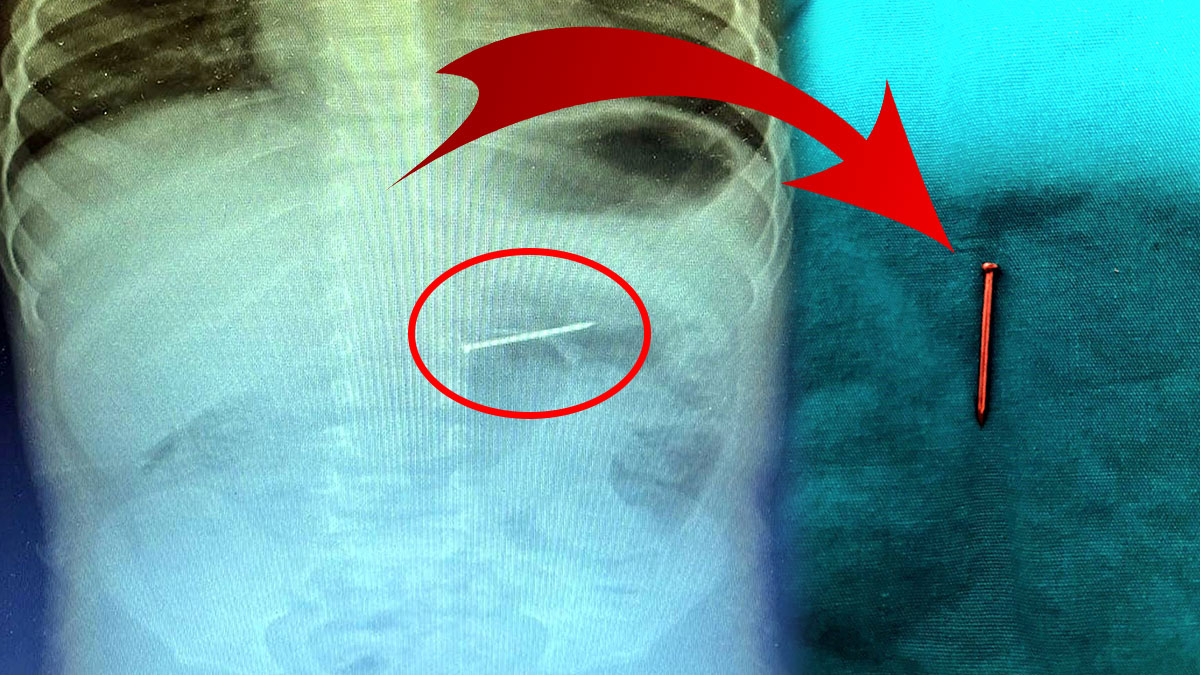

Yapılan radyolojik incelemeler sonucunda, yaklaşık 4 santimetre uzunluğundaki çivinin çocuğun midesinde olduğu tespit edildi.

Bu kritik durum karşısında hızla endoskopik müdahale kararı alındı. Başarılı bir operasyonla çivi, çocuğun sindirim sistemine herhangi bir zarar vermeden mideden çıkarıldı.